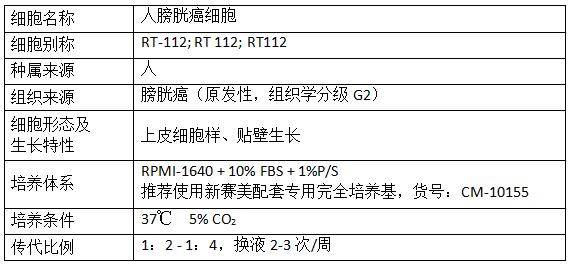

产品信息: